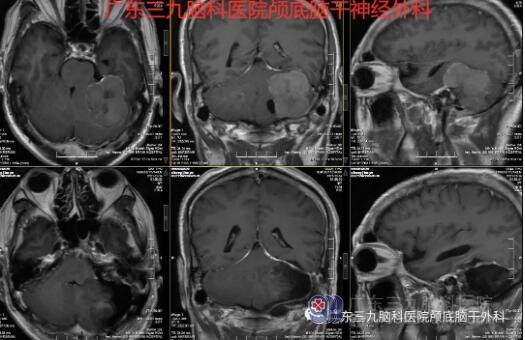

“患者脑膜瘤的位置在后颅窝左侧跨小脑幕上下,大小约49×48×49mm,此部位的脑膜瘤很常见,大部分质地软,容易切除。少部分质地硬,切除困难。”神经外一科主任张良介绍说。

针对患者的病情,神经外一科在科室主任张良的带领下,对患者的身体情况进行全面的术前讨论,制定了详细的手术方案,做好了充分的术前准备。与患者家属充分沟通后,于129号在全麻下行“左侧桥小脑角区脑膜瘤切除术”,术中注意保护后组神经、三叉神经和面瘫神经。整个术程顺利,病理报告示: (右侧桥小脑角)纤维型脑膜瘤,CNSWHO I级。